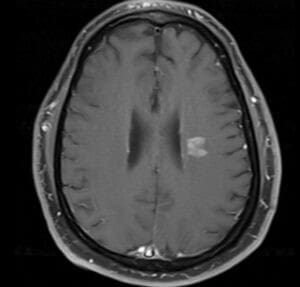

When symptoms persisted patient presented to his PCP, MRI was ordered and when MRI did show corona radiate enhancing lesion shown above, he was referred to ED again for further workup.

MRI: 1.5 cm corona radiata lesion on FLAIR image that enhance with contrast, no diffusion restriction. Multiple subcorictal and juxtacortical FLAIR hyper intense lesions but non-enhancing.

MRI reported as either subcortical infarction versus demyelinating disease versus lymphoma.